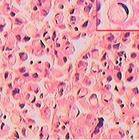

根据世界卫生组织分类,印戒细胞癌(SRCC)是一种组织学分型,这种分型最初是源于肿瘤的镜下特征而非其生物学行为,镜下显示肿瘤细胞胞质丰富、充满黏液,核被挤压于胞质一侧呈“印戒”样,因而得名,是一种特殊类型的黏液分泌型腺癌,常发生于胃肠道、乳腺、膀胱及前列腺等部分,而肺脏原发的SRCC却很少见。